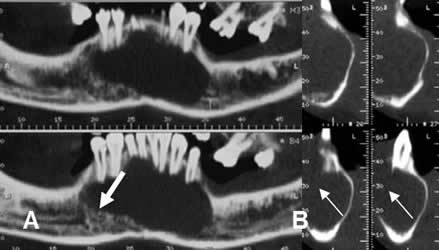

Fig 65. Ameloblastoma.

A: TAC en ventana de hueso, B: TAC axial en ventana de tejido, C: TAC reconstrucción coronal y D: TAC reconstrucción sagital. Lesión lítica y de comportamiento agresivo, que compromete la sínfisis y cuerpo de la mandíbula, con masa asociada de tejidos blandos.

Fig 66. Ameloblastoma.

A: TAC axial y B: TAC reconstrucción coronal en ventana de tejido y C: TAC reconstrucción sagital, en ventana de hueso. Masa de tejidos blandos, que expande el ángulo de la mandíbula. (Flechas delgadas). Esta lesión ocasiona ruptura de la cortical y corresponde a ameloblastoma. (Flecha gruesa).